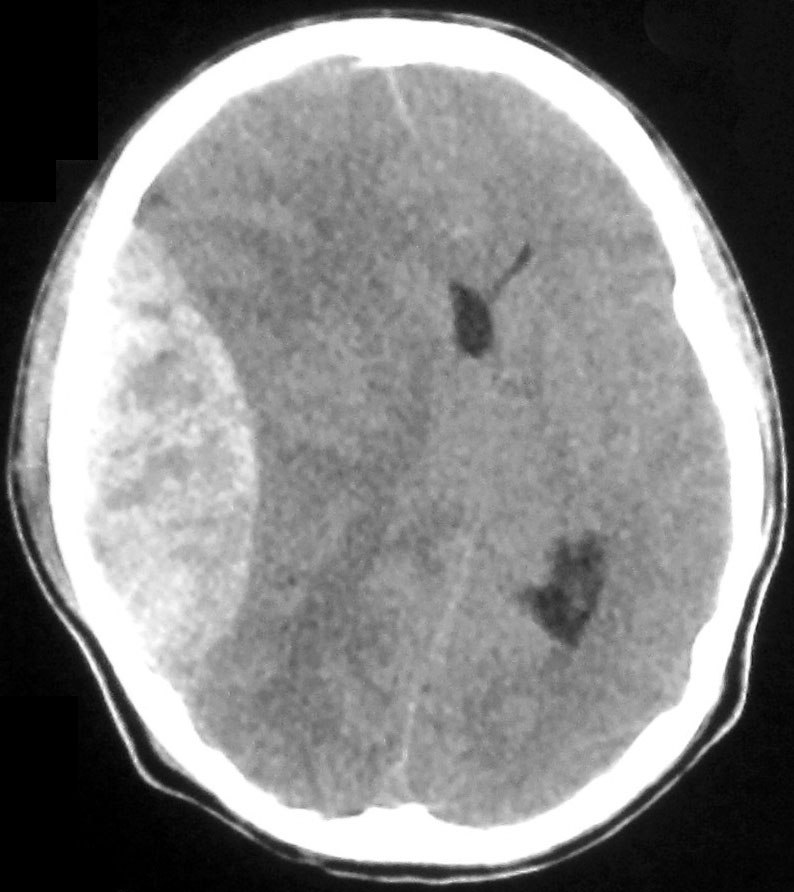

Медицинские аспекты и диагностика субдуральной гигромы мозга